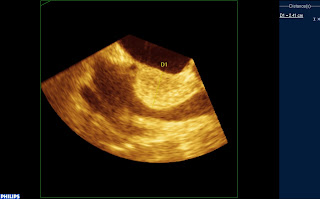

Coupe à 120° : VCS à droite de l’écran, fosse ovale au milieu :

La masse refoule la veine pulmonaire supérieure droite (en rouge en haut à droite) et la veine cave supérieure en bas à droite, mais sans envahissement :